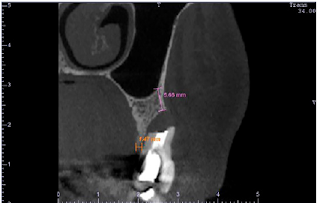

Figure 1: CBCT cross-sectional image of the tooth showing the complete loss of the buccal bone wall. The initial buccal bone height was of 5.66mm (magenta) and the crestal bone thickness was of 1.47mm (orange).

Prosthetically-driven alveolar reconstruction (PDAR) technique [1] is a method for alveolar ridge preservation/regeneration after tooth extraction and is indicated for extraction sockets with the absence of one bone wall (Figure 1) or even for an intact alveolus. It is based on alveolar occlusion, using a fixed provisional prosthesis with a specially designed pontic to provide stability to the coagulum and mechanical support to the gingival margin, preventing mucoperiosteal collapsing. There are some prerequisites when performing PDAR: teeth neighboring the compromised tooth area should be healthy and without proximal bone loss, and in esthetic areas, the gingival margin should be in harmony with the surrounding teeth and its contralateral counterpart. PDAR has a number of advantages, such as preservation of the preexisting alveolar bone by avoiding realizing incisions and flaps; regeneration of lost alveolar bone without the use of grafts or membrane barriers; and new bone formation in the space left by the tooth root using a minimally invasive procedure.